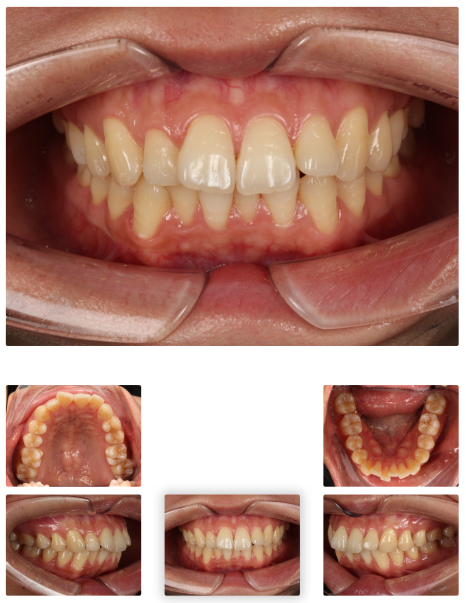

< 인비절라인 돌출입 교정 사례 중 일부>

치료기간: 24.12.13 - 진행 중